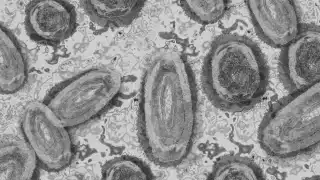

OMS y ONU buscan crear reserva de vacunas contra viruela mpox

La OMS y la ONU anunciaron que, ante los brotes de casos de viruela mpox, han decidido crear una reserva de vacunas contra este virus

La Organización de las Naciones Unidas (ONU) y la Organización Mundial de la Salud (OMS) dieron a conocer que buscarán que se cree una reserva de vacunas en contra de la viruela mpox, esto con el objetivo de atender a los países de bajos ingresos.